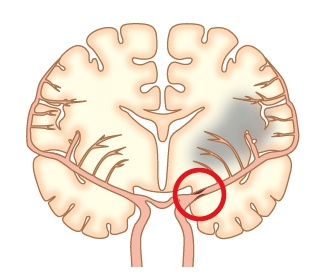

2)アテローム血栓性脳梗塞

脳に行く太い血管が、粥状硬化性病変(アテローム:コレステロールなどの塊)により細くなるか詰まって血流が足りなくなり起こす脳梗塞です。中高年で動脈硬化の危険因子(高血圧症、糖尿病、脂質異常症、喫煙、肥満)を持っている方に多く見られます。血管が詰まる場所により症状や重症度は様々です。状態によっては病状が落ち着いてから手術やカテーテルの治療が行われることがあります。